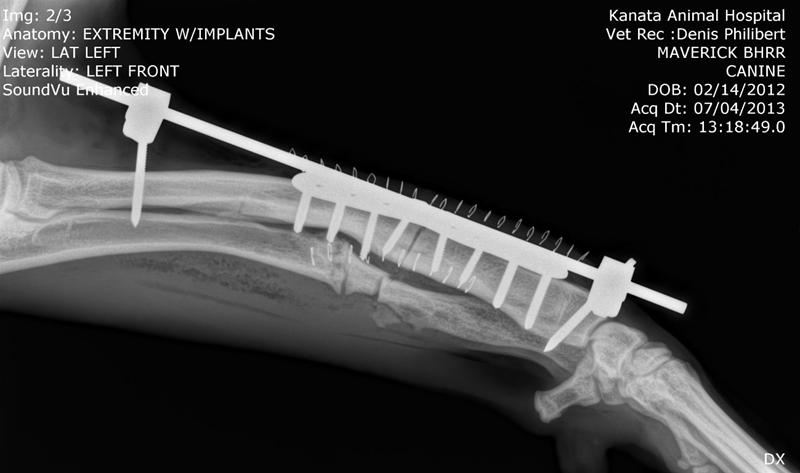

BHRR's Maverick, TTP – June 15th, 2013 & BHRR's Maverick – July 4th, post-op surgery

AND, here are his x-rays!